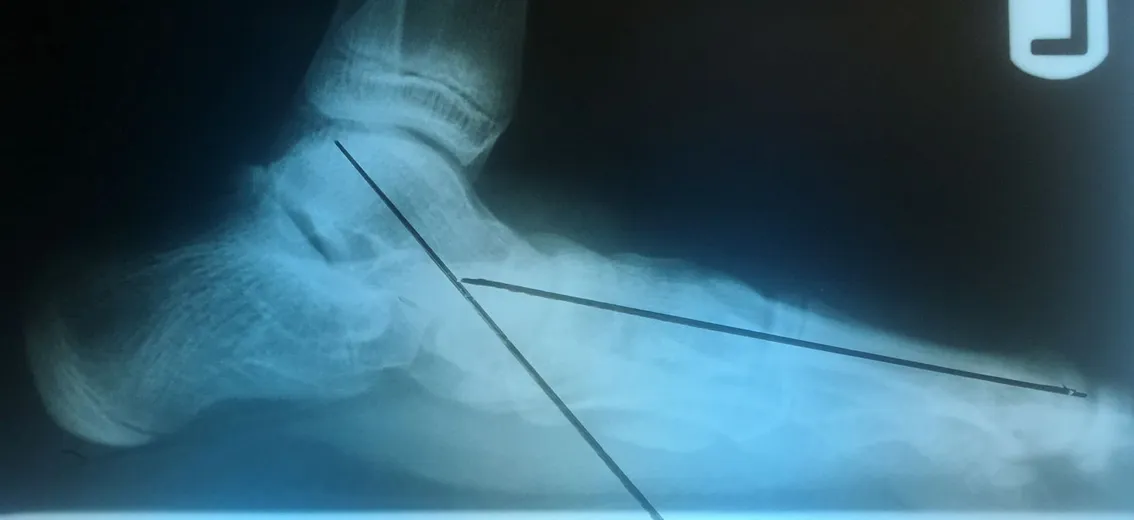

Below are x-rays of a foot pre-operatively (left) where the black line indicates and plantarflexed (downward directed) talus bone and post-surgical repair with a subtalar joint implant and lenthening of the calf muscle which allows the calcaneus (heel bone) to set underneath the talus and the implant keeps the talus from subluxing off the calcaneus and now the talus is more inline with the front of the foot (right).